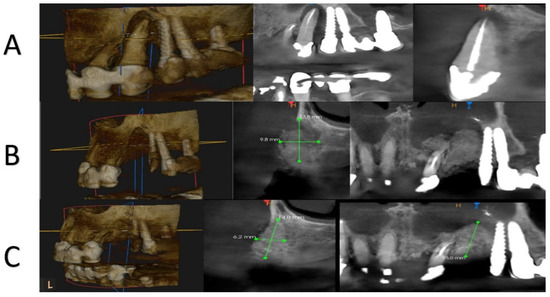

2.4. Surgical Procedure (In Vivo)

2.5. Bone Biopsies (In Vivo)

2.6. Histological Procedure (In Vitro)

3.2. Histological Evaluation of Graft Integration with Bone Tissue

3.3. Evaluation of Healing Process